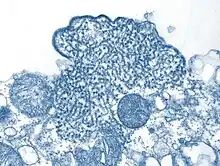

Structure of a Henipavirus | |